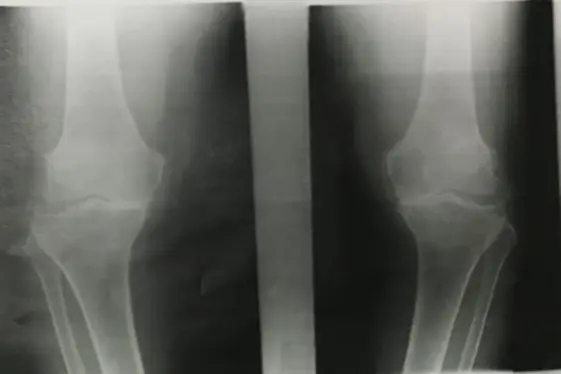

| Look | Compare both limbs, Skin, Muscle bulk, bony landmarks, hair distribution | Assess symmetry, signs of trauma, inflammation, muscle atrophy, structural changes | Visual examples - Skin, Muscle, Bone, Joint: ![]() ![]() ![]() ![]() ![]() ![]() | Swelling, scars, discoloration, hair changes, muscle wasting, bony protrusions, angulation, redness |

| Flexion & Extension (Normal: Extension: 0° → Flexion: 140°) | Quantify the knee’s range of motion | Extension: Flexion: ![]() | Reduced or excessive range of motion; “lacks X degrees of extension” | |